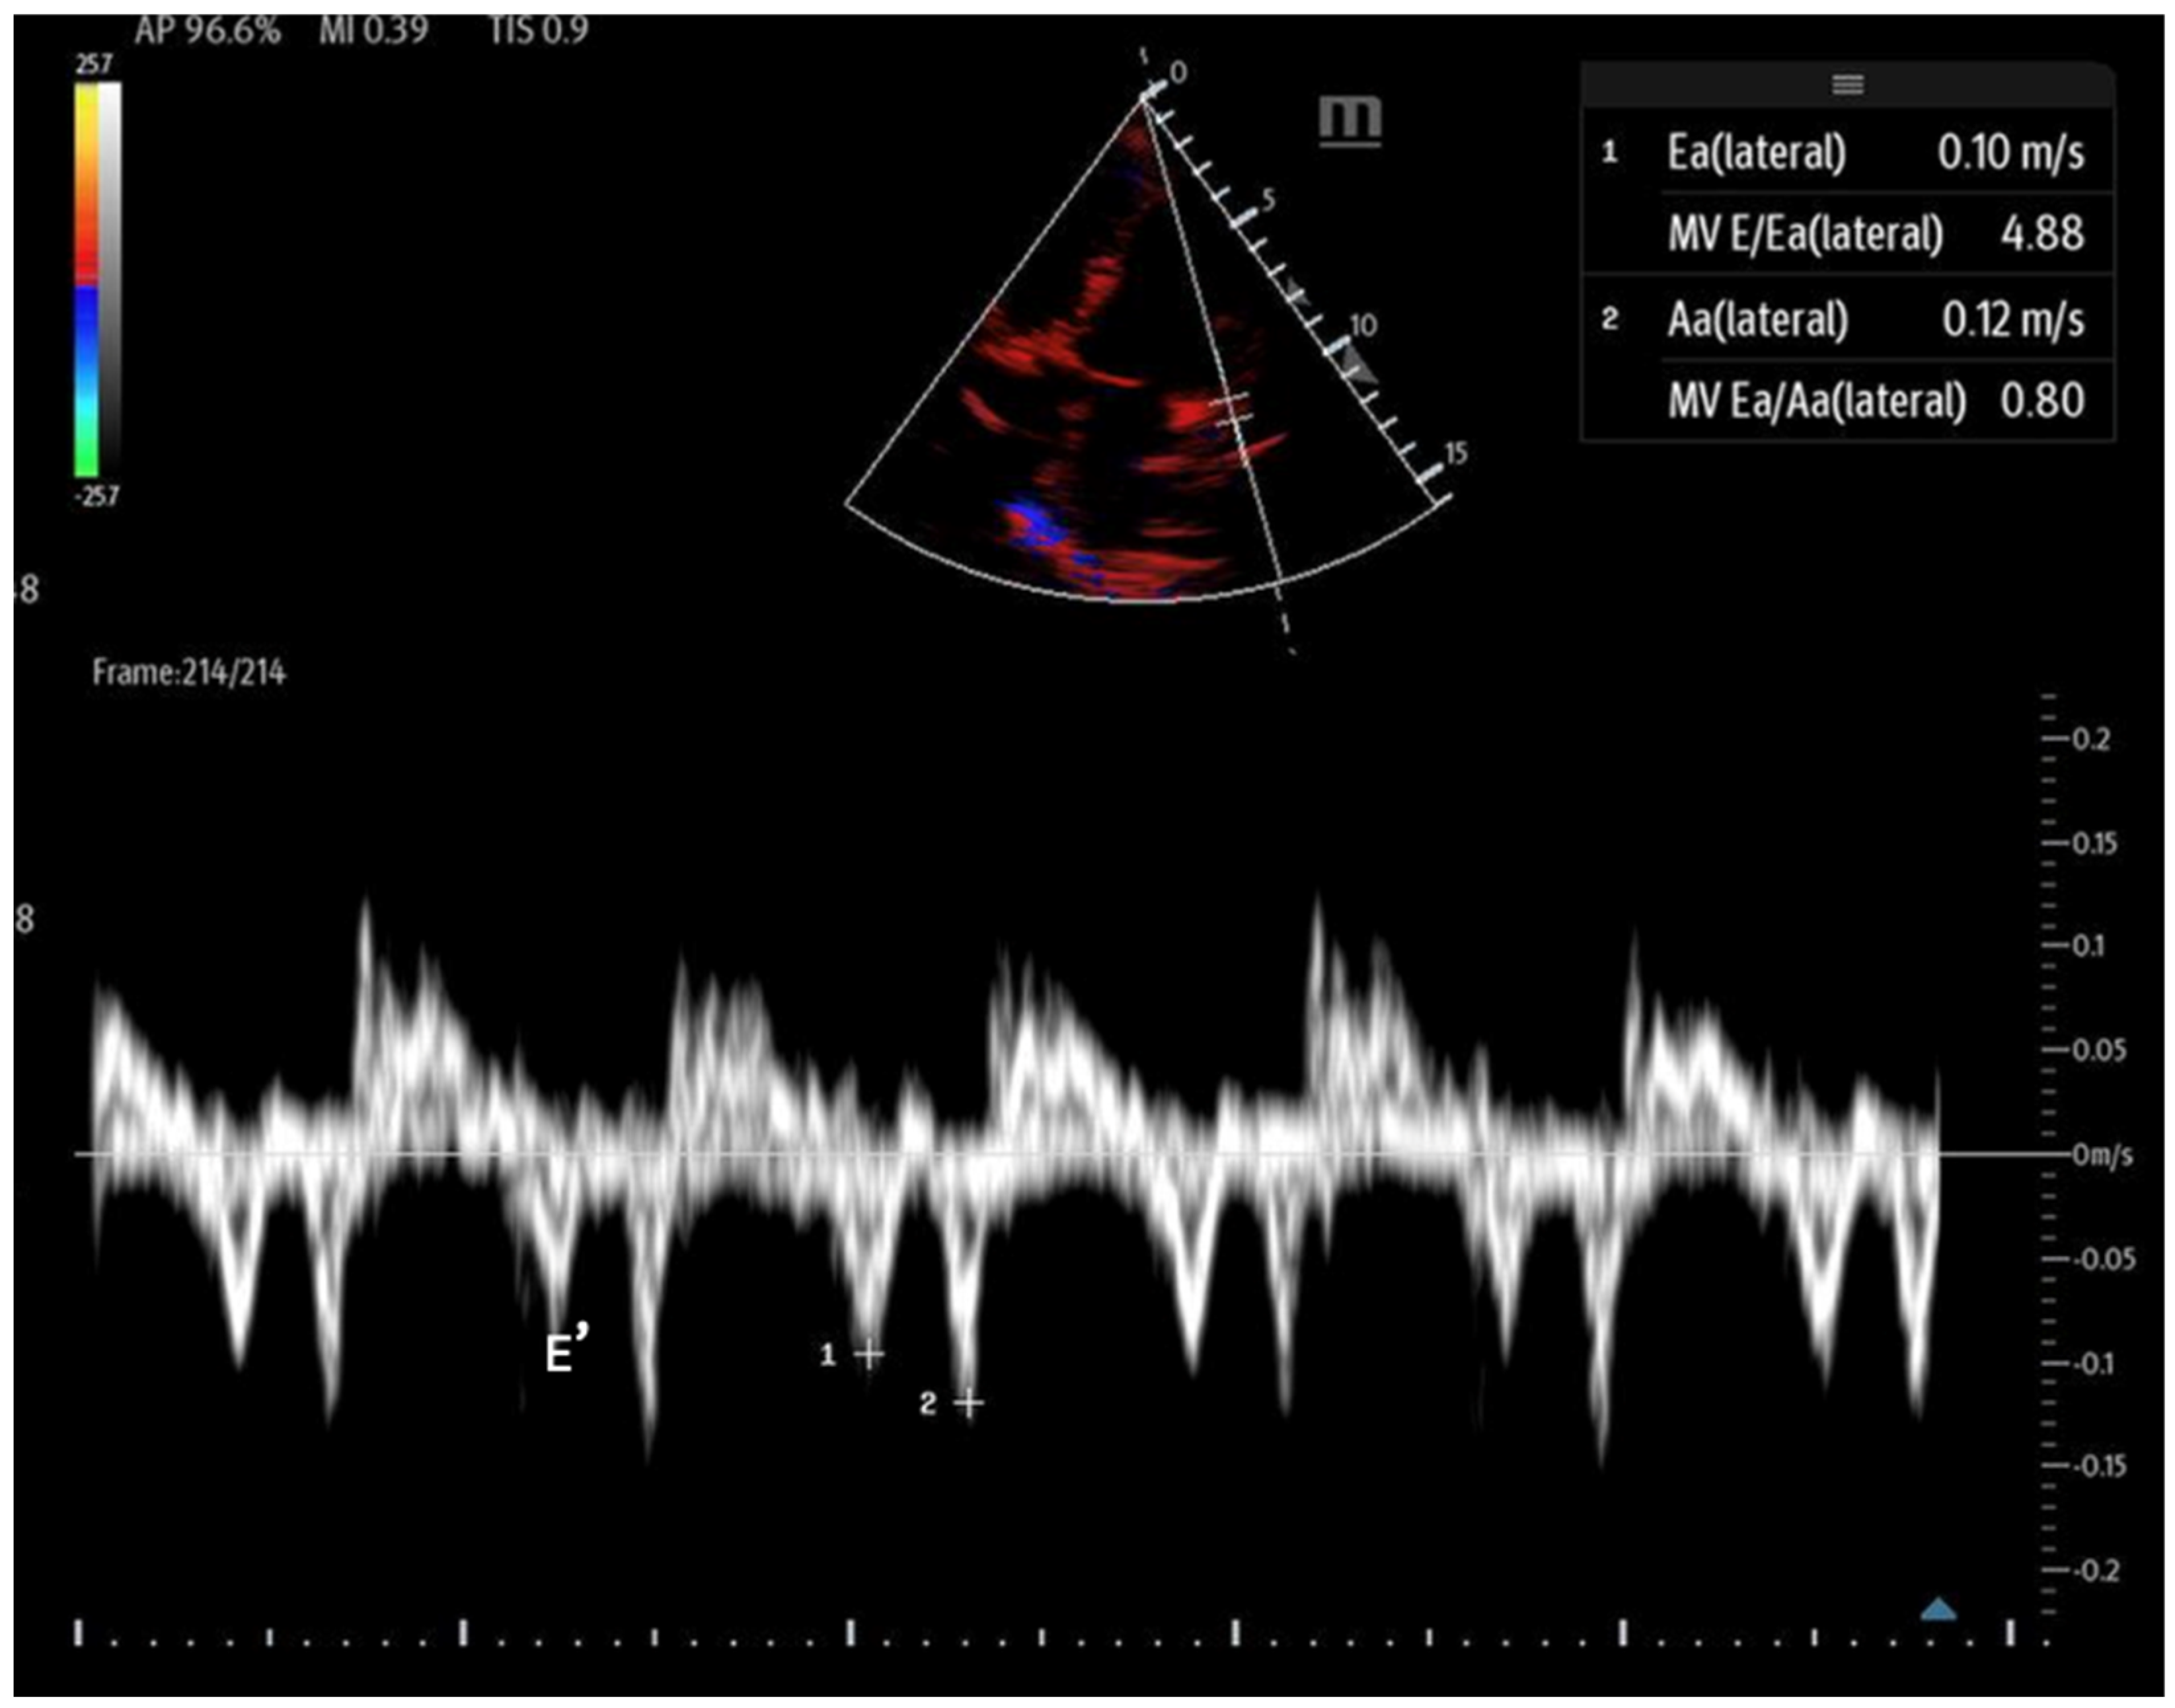

- Mitral inflow: Assessed via pulsed-wave (PW) Doppler at the mitral valve tips in the apical four-chamber view, this measures the blood flow velocities entering the left ventricle as an upward deflection of the PW Doppler signal. The resultant E and A waves are then evaluated for their ratio (Figure 14).

Figure 14. Mitral inflow with PW Doppler gate at mitral valve tip (E and A waves). - Tissue Doppler: Measures myocardial movement during diastole using tissue Doppler at the septal annulus. The E/e′ ratio is calculated from the recorded e′ wave (Figure 15).

Figure 15. Tissue Doppler at the lateral septal annulus to record the E′ wave (labeled).

When abnormal, these values can indicate diastolic dysfunction and its severity (Table 3). However, certain factors, such as mitral annular calcification, basal wall motion abnormalities, mitral stenosis, and significant mitral regurgitation, can affect mitral inflow velocities and invalidate measurements. Additionally, tachycardia may cause the fusion of the E and A waves, and atrial fibrillation can lead to variable RR intervals, further complicating accurate assessment [63]. It is important that while these assessments can be performed with bedside POCUS, accurately interpreting advanced diastolic parameters often exceeds the scope of non-cardiologist operators and may necessitate formal transthoracic echocardiography.